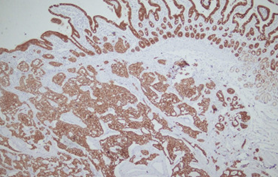

Immunohistochemical evaluation demonstrated positivity for parathyroid hormone and chromogranin, with low mitotic and proliferative activity (Courtesy Dr. V. Penopoulos)